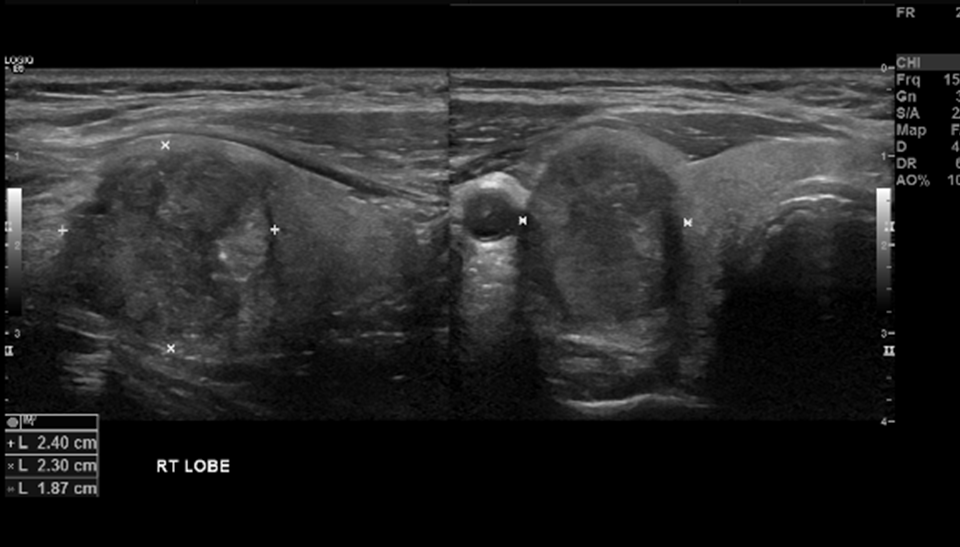

Узи tirads 3

Узи tirads 3 100 фотографий